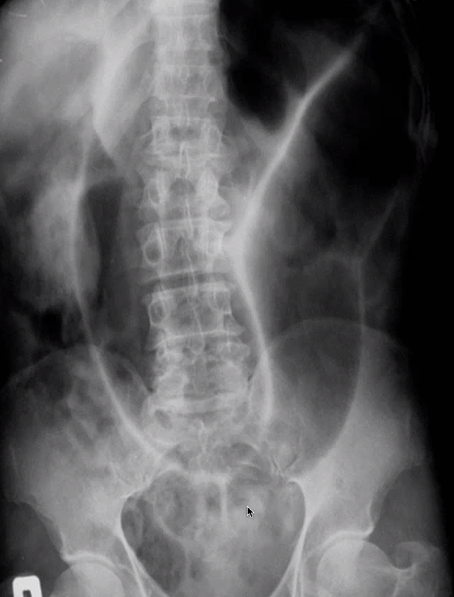

type of imaging

pathology

AXR

sigmoid volvulus